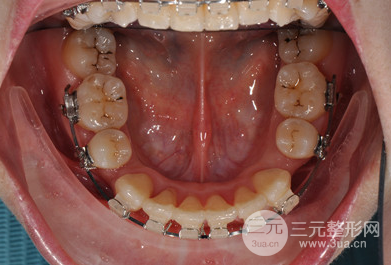

對(duì)一次緩解拔了四顆智齒,太專業(yè)的緩解矯正過程我也說不上來,只知道為了減輕牙齒之間的擁擠程度,不得不拔牙,其實(shí)我的凸嘴不算特別嚴(yán)重,在拔牙之后做矯正固定就可以了,但是既然選擇了做整形就要做到很好的果,所以在醫(yī)生的專業(yè)保障下做了牙齒正畸,開始了我的漫長牙套之路。

在做牙齒正畸這段時(shí)間里,一直都堅(jiān)持飲食清淡和清潔工作,不能過度咀嚼,所以在著兩年多的堅(jiān)持下還是有很明X的改良的。

矯正期間沒個(gè)一段時(shí)間就要回醫(yī)院做復(fù)查和更換牙套,好在醫(yī)生的技術(shù)比較好,牙齒矯正比較爭氣,現(xiàn)在想過很滿意,不僅沒有凸嘴,牙齒也很整齊,現(xiàn)在已經(jīng)取了牙套之后可以隨意吃吃喝喝了,這兩天沒有白堅(jiān)持。